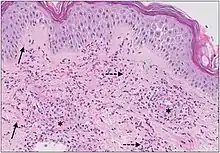

The small vessels in the skin affected are located in the superficial dermis and include arterioles (small arteries carrying blood to capillaries), capillaries, and venules (small veins receiving blood from capillaries).[5] In general, immune complexes deposit in vessel walls leading to activation of the complement system. C3a and C5a, proteins produced from the complement system, attract neutrophils to the vessels.[9] Once activated, neutrophils then release preformed substances, including enzymes causing damage to vessel tissue.[9] Evidence of this process can be seen with a sample of removed skin tissue, or biopsy, viewed under a microscope. Neutrophils are seen surrounding blood vessels and their debris within vessel walls, causing fibrinoid necrosis. This finding on histological examination is termed "leukocytoclastic vasculitis".[5]